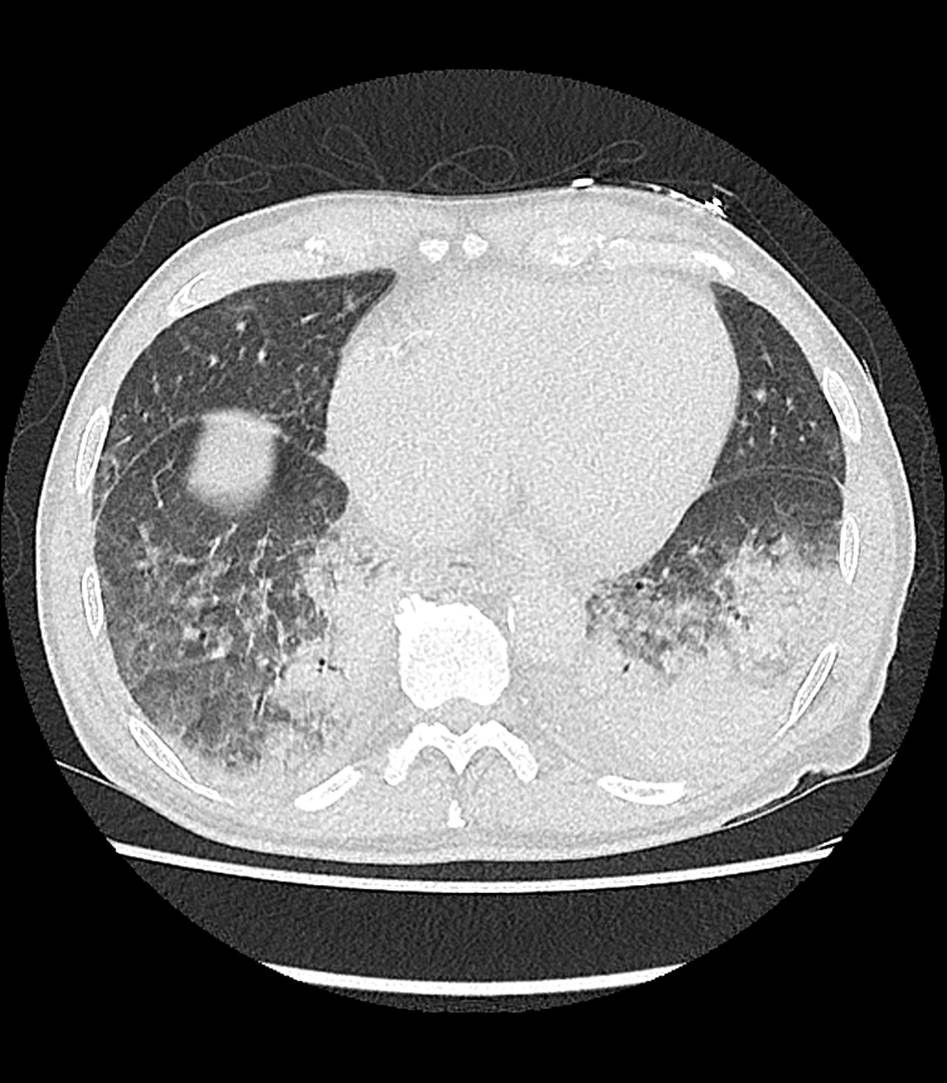

„Die Computertomographie ist bei der Diagnose der Patienten mit Verdacht auf eine Corona-Erkrankung eine wertvolle Hilfe“, sagt Prof. Dr. Dierk Vorwerk, Leiter des Zentrums für Radiologie und Neuroradiologie im Klinikum Ingolstadt. Bei etwa der Hälfte der Betroffenen lassen sich die Anzeichen auf eine Covid-19-Infektion bereits ab dem dritten Tag nach Ansteckung feststellen – und das innerhalb von wenigen Sekunden. Ein Abstrich zeige üblicherweise erst nach fünf Tagen an, ob ein Patient Covid-19 positiv ist, die Auswertung des Testergebnisses benötigt zusätzlich Zeit. Trotzdem sei die CT-Aufnahme der Lunge keinesfalls ein Ersatz für einen Labortest. Mit dem CT lassen sich lediglich die für Covid-19 typischen Veränderungen feststellen. „Ein Abstrich findet immer zusätzlich zur CT-Untersuchung statt“, so Prof. Vorwerk. Ist ein Patient an Covid-19 erkrankt, zeigt sein CT-Bild häufig wolkenartige Verdichtungen in den Außenbereichen der Lunge. Diese Milchglastrübungen seien typisch – aber nicht spezifisch – für die Krankheit.